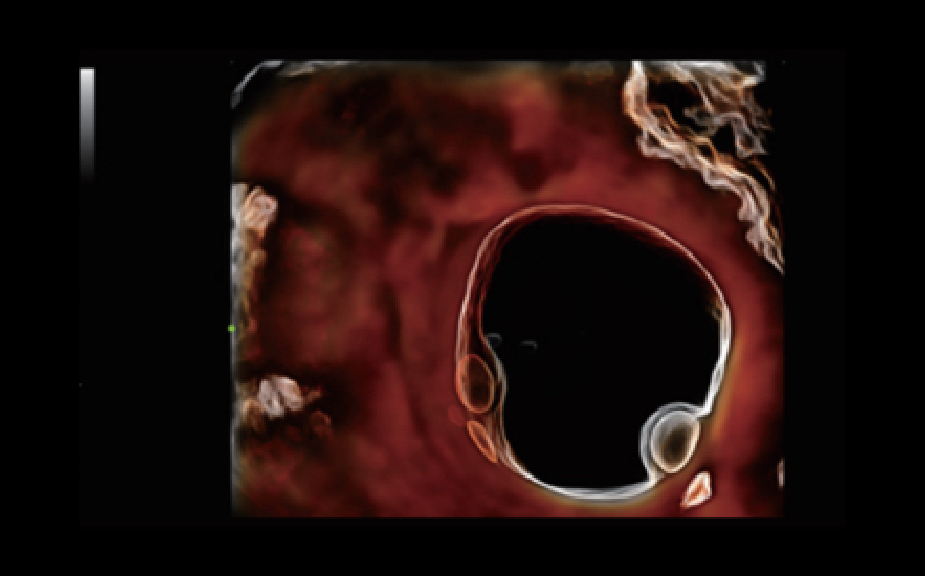

Clinical Images